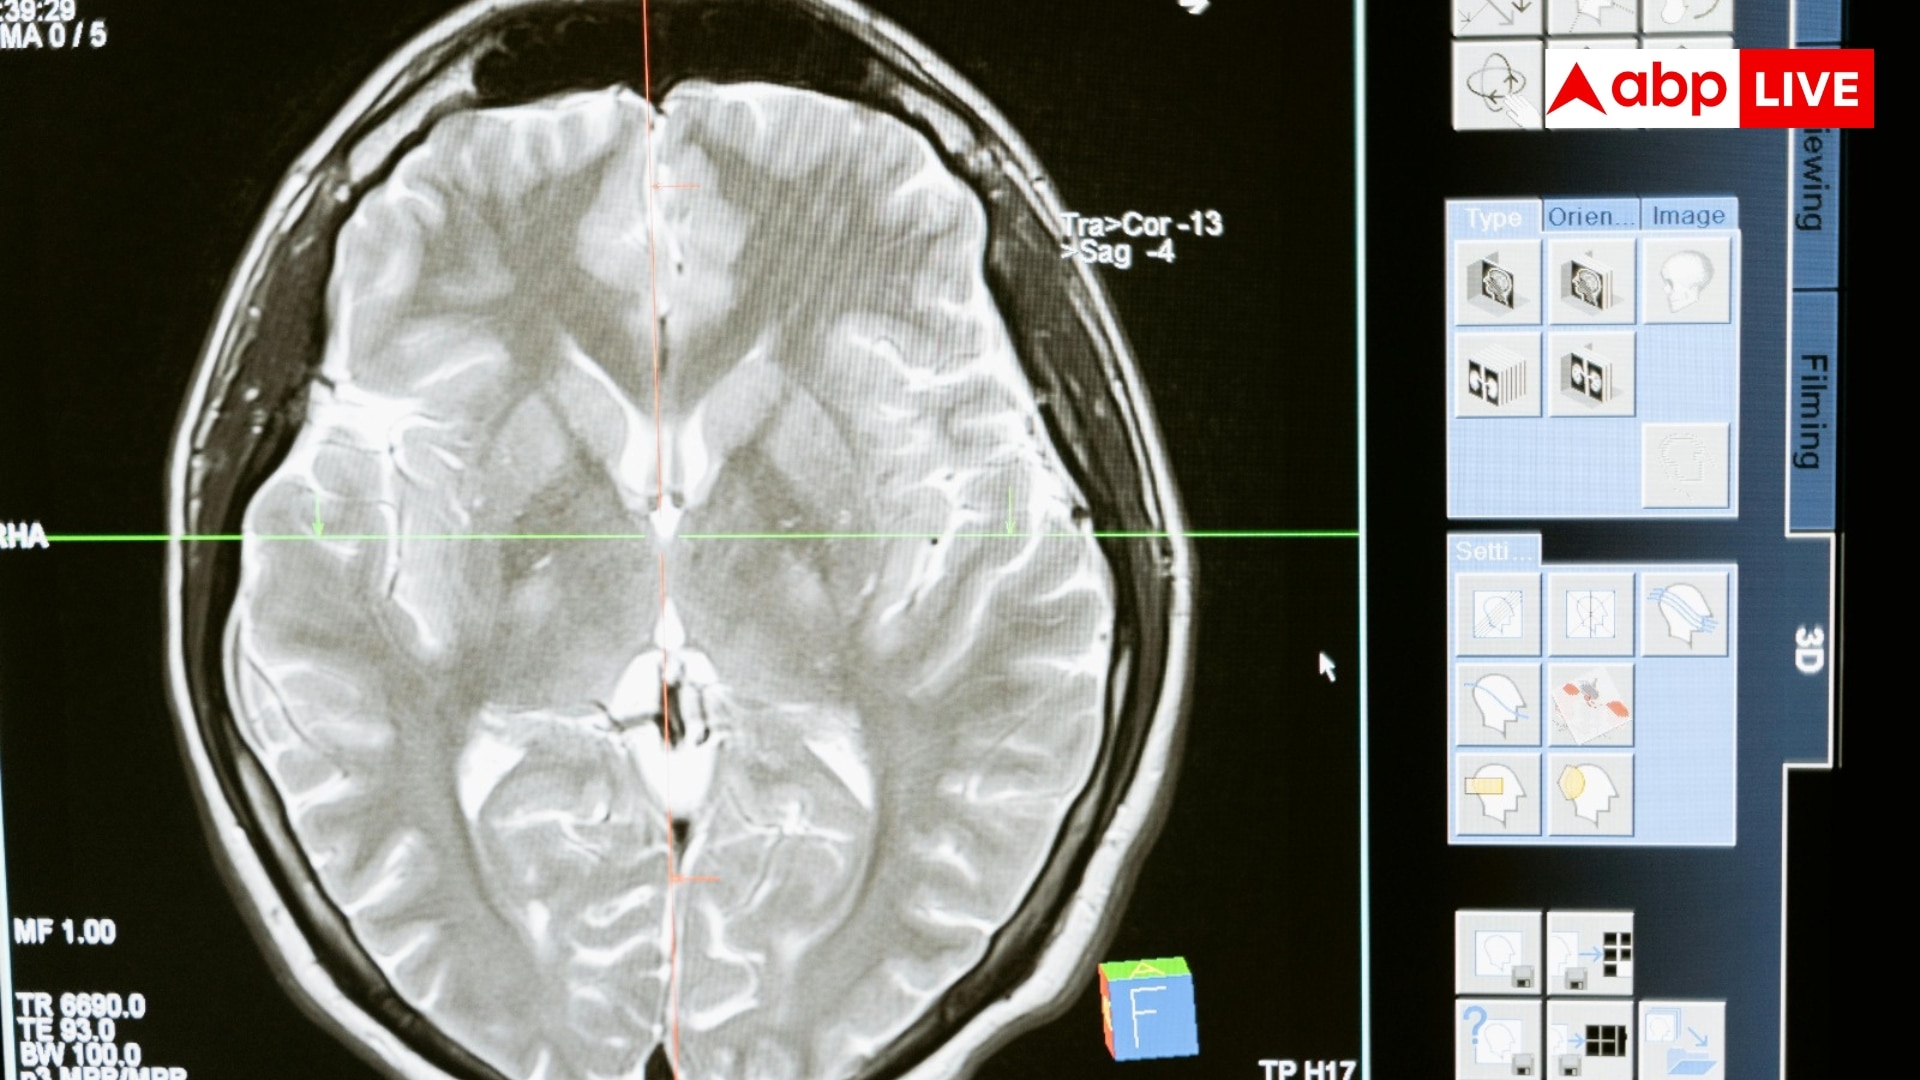

पुरुषों से ज्यादा महिलाओं में होता है अल्जाइमर का रिस्क, स्टडी में चौंकाने वाला खुलासा